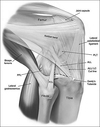

Arthroscopic image of a knee shows the posterior cruciate ligament bundle origins. The anterolateral bundle (ALB) and the posteromedial bundle (PMB) are observed at their origin on the lateral side of the medial femoral condyle (MFC), or the medial intercondylar notch.

A

• primary restraint to posterior tibial translation, greatest instability at 90 of flexion.

• AL tight in flexion, strongest/most important for stability at 90 “PAL” PCL

• PM tight in extension.